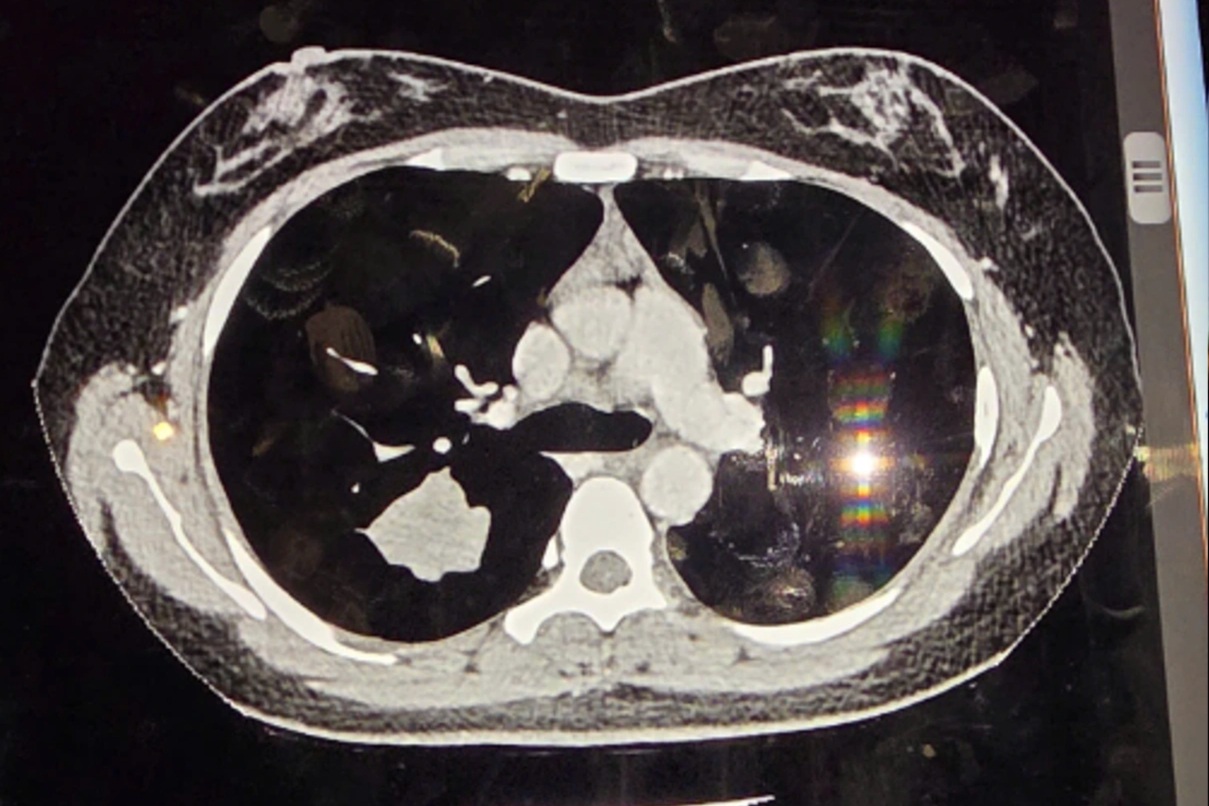

Thực phẩm bẩn đang trở thành một trong những vấn nạn nhức nhối nhất ở Việt Nam hiện nay. Thực phẩm bẩn gây ra những hiểm họa rình rập đe dọa sức khỏe. Theo các chuyên gia ung bướu của Việt Nam, hơn 30% ca ung thư bắt nguồn từ các thực phẩm bẩn chứa chất gây ung thư. Một trong những cách hữu hiệu để bảo vệ chính mình và người thân trước hiểm họa ung thư chính là định kỳ khám sàng lọc để phát hiện sớm ung thư theo hướng dẫn của thầy thuốc.